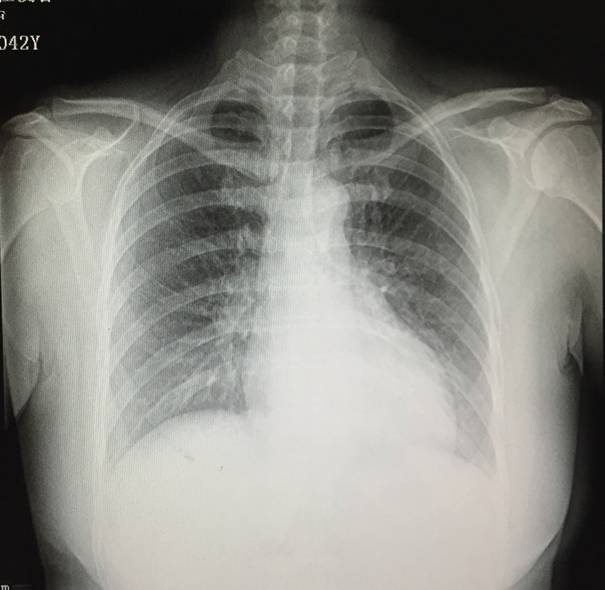

全胸片

◆扩张性心肌病

◆完全性左束支传导阻滞